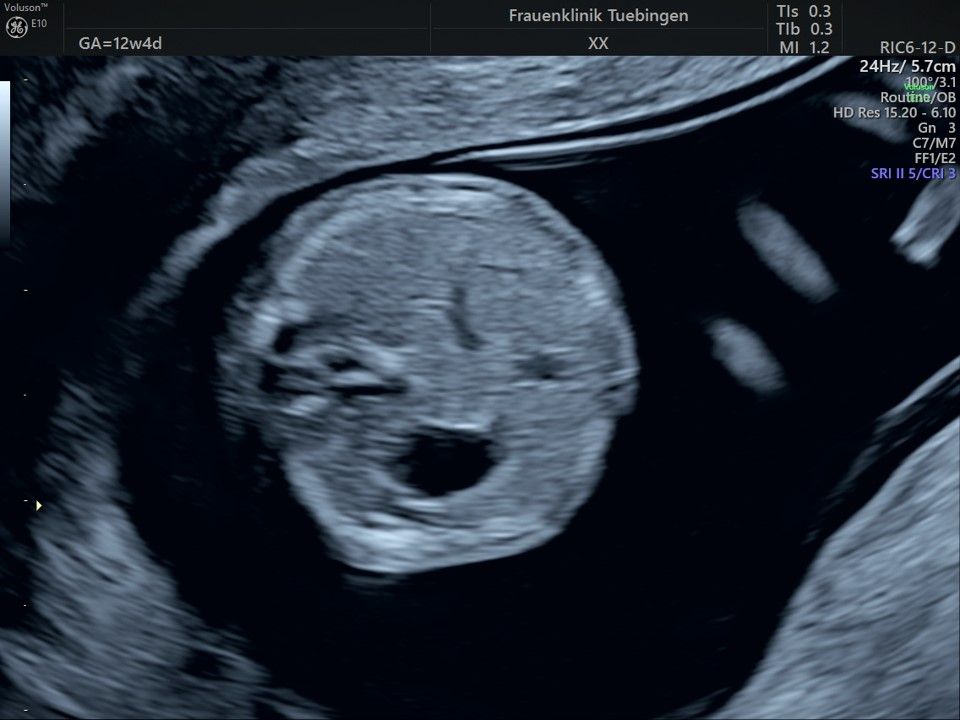

Im Rahmen des Ersttrimester-Screenings untersuchen wir die Organe des Feten mittels Ultraschall. Dabei machen wir auch gerne ein Bild für Sie.

Obwohl der Fet zu diesem Zeitpunkt erst zwischen 5 und 8cm groß ist, lassen sich bereits etwa die Hälfte aller schwerwiegenden Fehlbildungen erkennen bzw. ausschließen. Sollten wir eine Auffälligkeit sehen, werden wir mit Ihnen den Befund und das weitere Vorgehen ausführlich besprechen.

Fetale Anatomie

Das Ergebnis der Ultraschalluntersuchung ist wegweisend. Dabei wird der Fet vermessen, die Organe werden untersucht und die sonographischen Marker zur Risikoberechnung für Chromosomenstörungen werden beurteilt. Das sind: die Nackentransparenzdicke, Nasenbein sowie der Blutfluss in der rechten Herzhälfte und im Ductus venosus, einem Gefäß in der Leber des Feten.